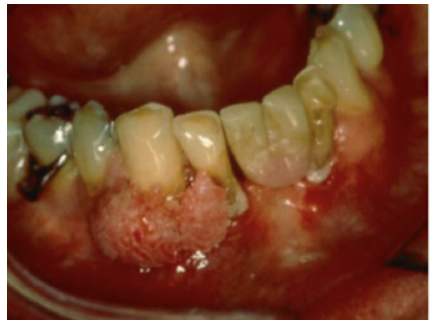

Pyogenic Granuloma

Hyperplasia of **capillaries**=RED color Cause: * Chronic trauma or irritation Gingiva=most commn